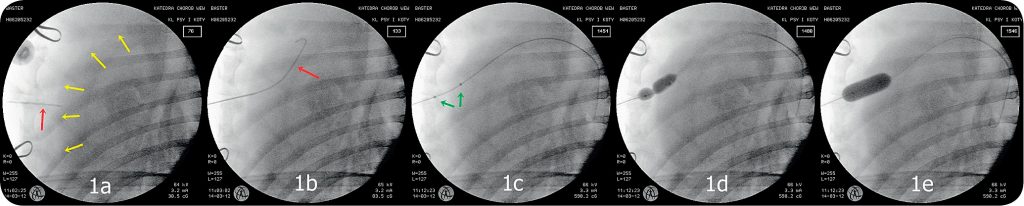

Pacjenta przed procedurą układamy na mostku lub nieznacznie przechylamy na prawą stronę. Po dokonaniu wyboru miejsca wkłucia znieczulamy nasiękowo okolicę ściany klatki piersiowej. Pod kontrolą USG i/lub fluoroskopu nakłuwany worek osierdziowy igłą atraumatyczną, na którą koniecznie musimy mieć założoną strzykawkę, aby nie doprowadzić do przypadkowej odmy opłucnowej po przejściu przez ścianę klatki piersiowej (ryc. 1a).

Obecność płynu w [...]